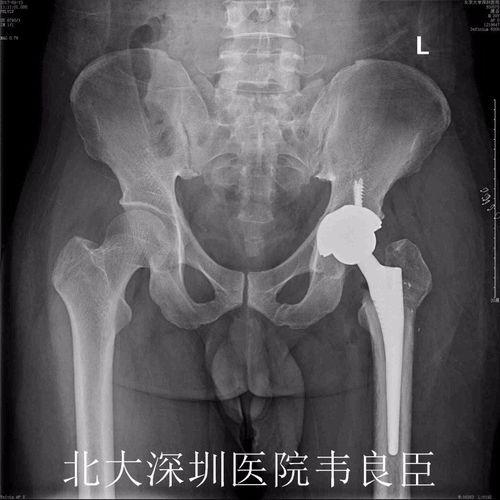

在手术之前,医生会为你进行一系列的检查,以确保手术的顺利进行。这些检查包括但不限于X光、CT扫描和血液检查。通过这些检查,医生可以了解你的髋关节状况,评估手术的可行性。

置换股骨头手术通常分为两个部分:股骨头置换和髋臼置换。下面,我们就来详细了解一下手术过程。

首先,医生会在患者的髋关节处切开一个小口,然后取出坏死的股骨头。接着,医生会植入一个新的股骨头,这个股骨头通常由金属制成,具有良好的生物相容性。

视频中,我们可以看到医生正在小心翼翼地取出坏死的股骨头,并植入新的股骨头。手术过程中,医生需要确保新股骨头与髋臼紧密贴合,以恢复髋关节的正常功能。

在完成股骨头置换后,医生会继续进行髋臼置换。首先,医生会在髋臼处切开一个小口,然后取出坏死的髋臼部分。接着,医生会植入一个新的髋臼,这个髋臼通常由陶瓷或金属制成。

视频中,我们可以看到医生正在为患者植入新的髋臼。手术过程中,医生需要确保新髋臼与股骨头紧密贴合,以恢复髋关节的正常功能。